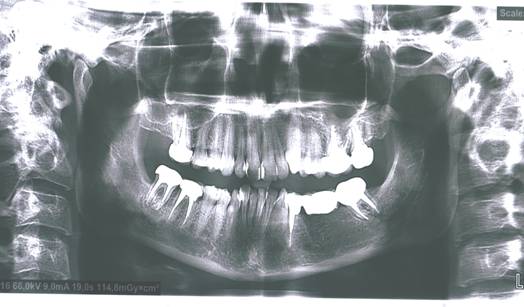

После проведенного лечения рекомендованы выполнение панорамной рентгенографии и

плановые осмотры 2 раза в год. Рис. 2

Рис.2 Панорамная

рентгенография пациентки Р., после проведенного лечения.

Восстановление и

стабилизация прикуса осуществлялась при помощи мостовидного

металлокерамического протеза с опорой на 34 – 37 зубы и встречными

металлокерамическими коронками на 16, 46, 47, 26, 27 зубы. Выравнивание окклюзионной кривой

левой и правой сторон позволило изменить положение головок ВНЧС. С левой

стороны, после проведенного лечения, появилась видимая суставная щель, которая

практически не прослеживалась при анализе исходной панорамной рентгенографии.

Это свидетельствует о нормализации окклюзионных взаимоотношений зубов верхней и

нижней челюстей.